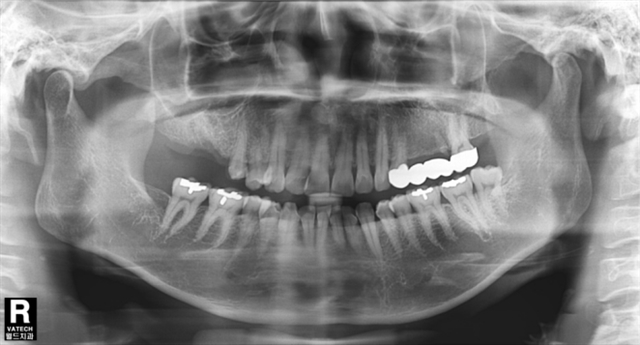

姓名:陈虹 年龄:52岁 性别:女性

现病史:右上后牙缺失4月,要求恢复。

既往史:右上单颗后牙缺失3余年,3年前曾于外院行烤瓷连冠修复治疗。4月前,右上烤瓷桥松动,咀嚼痛,遂于我科就诊去除烤瓷连冠,拔除右上折裂基牙。既往体健,否认高血压,糖尿病病史。

诊断:上颌牙列缺损

缺损部位: 右上颌后牙

拔牙前

拔牙后